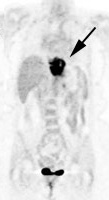

Images of Esophagus Cancer

PET for case on the left